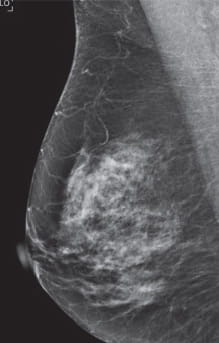

Breast Density Heterogeneously Dense

Category C: Heterogeneously dense